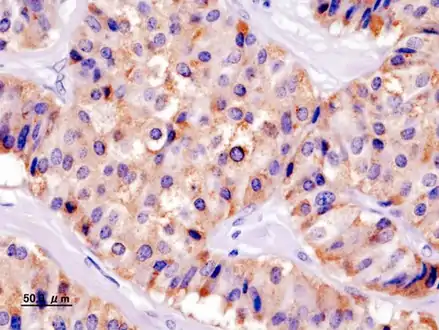

Insulin immunostain